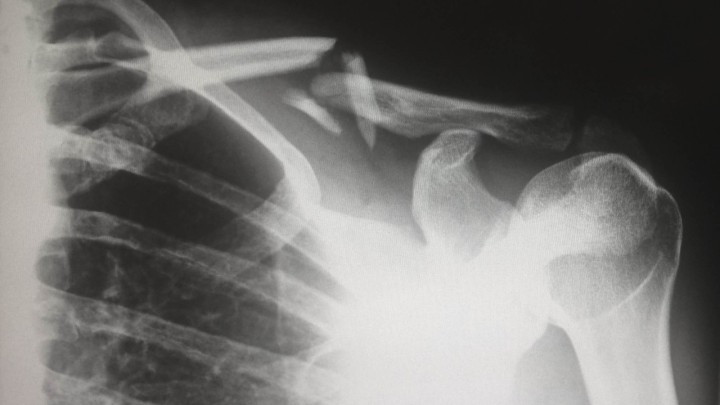

Osteoporoza: Nevidljiva bolest koja pogađa više od 117.000 Hrvata